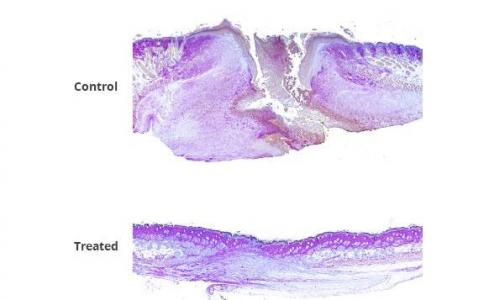

La preuve chez la souris : la combinaison FL2-siRNAs / PluroGel appliquée à des souris présentant des excisions cutanées ou des brûlures permet, à 4 jours post-traitement, de réduire la taille de la plaie d’excision de moitié. Plusieurs souris traitées par la thérapie combinée présentent également des follicules pileux sur l’ex site de la plaie, alors qu'aucun n’est observé chez les souris témoins. Et, chez les souris traitées pour brûlures, 14 jours après la lésion, les plaies des souris traitées sont réduites d’environ un tiers. En outre, les plaies de brûlure de toutes les souris traitées avec la combinaison FL2-siRNA / PluroGel sont totalement cicatrisées à 14 jours, vs seulement 25% à 30% chez les souris témoins.

Une cicatrisation plus rapide et plus complète, mais induisant une « régénération réelle », avec restauration des réseaux de collagène de soutien de la peau, et repousse des follicules pileux : les chercheurs newyorkais décrivent ainsi des améliorations cliniquement importantes sans précédent dans le traitement des plaies. L’auteur principal, le Dr David J. Sharp, professeur de physiologie et biophysique à Einstein, commente : « Nous prévoyons que cette thérapie aura une large application pour toutes sortes de plaies, des coupures aux blessures en passant par les plaies chroniques ».